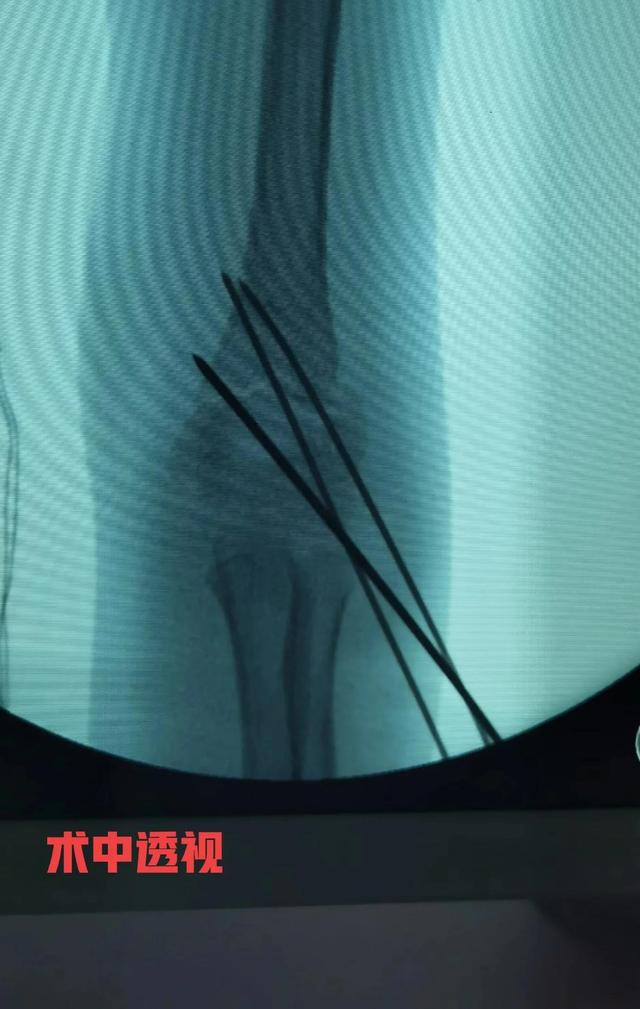

病例 女性,7岁,跌伤,右肱骨髁上骨折